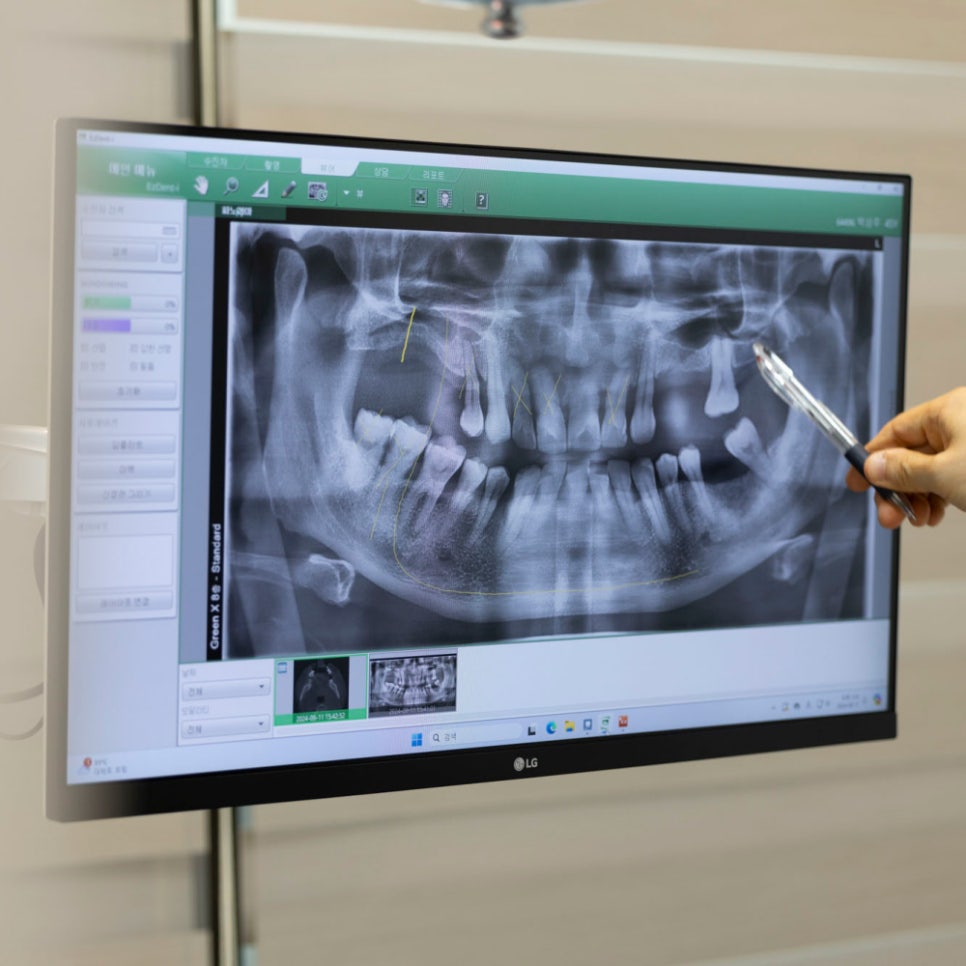

임플란트 회복기간은 몇 개월 정도 기다려야 하나요?

임플란트 회복기간은 개인마다 조금씩 차이가 있는데요.

평균적으로 상악이라고 부르는 위턱은 약 4~5개월 정도,

하악인 아랫턱은 약 2~3개월 정도 소요됩니다.

위턱은 상대적으로 뼈가 부드러워서 초기 고정력이 약하고,

혈류량이 적은 편이라 회복 속도도 다소 느린 편인데요.

특히 상악동(부비동)이라고 하는 뼛속 빈 공간과 맞닿아있어

상악동 거상술이라는 부가적인 수술이 필요한 경우도 많죠.

이 경우 임플란트 회복기간이 당연히 늘어날 수 밖에 없습니다.

반면에 아래턱은 위턱에 비해 잇몸뼈가 단단하고 치밀해서

임플란트가 식립된 후 안정적으로 고정되기 쉬운 편인데요.

또한, 혈액 공급도 더 원활하고 구조적인 제약이 적기 때문에

위턱에 비해 치료도 단순하고 임플란트 회복기간이 빠른 것이죠.